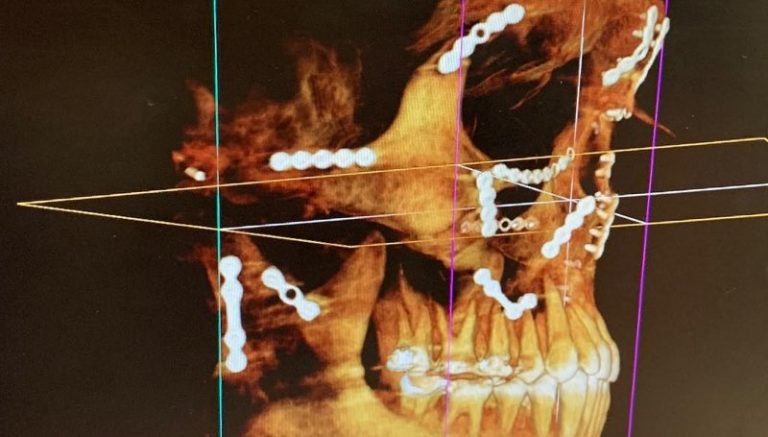

Weston Peick mostra a reconstrução do seu rosto

Weston Peick mostrou o quanto de trabalho foi necessário para reconstruir seu rosto após o acidente no Supercross de Paris, em novembro.

“21 placas quatro parafusos e um enxerto ósseo”, disse Peick sobre a cirurgia que ele teve que suportar após ser atropelado no primeiro main event da noite. Peick se recuperou bem, mas não foi divulgado se ele poderá voltar a competir.